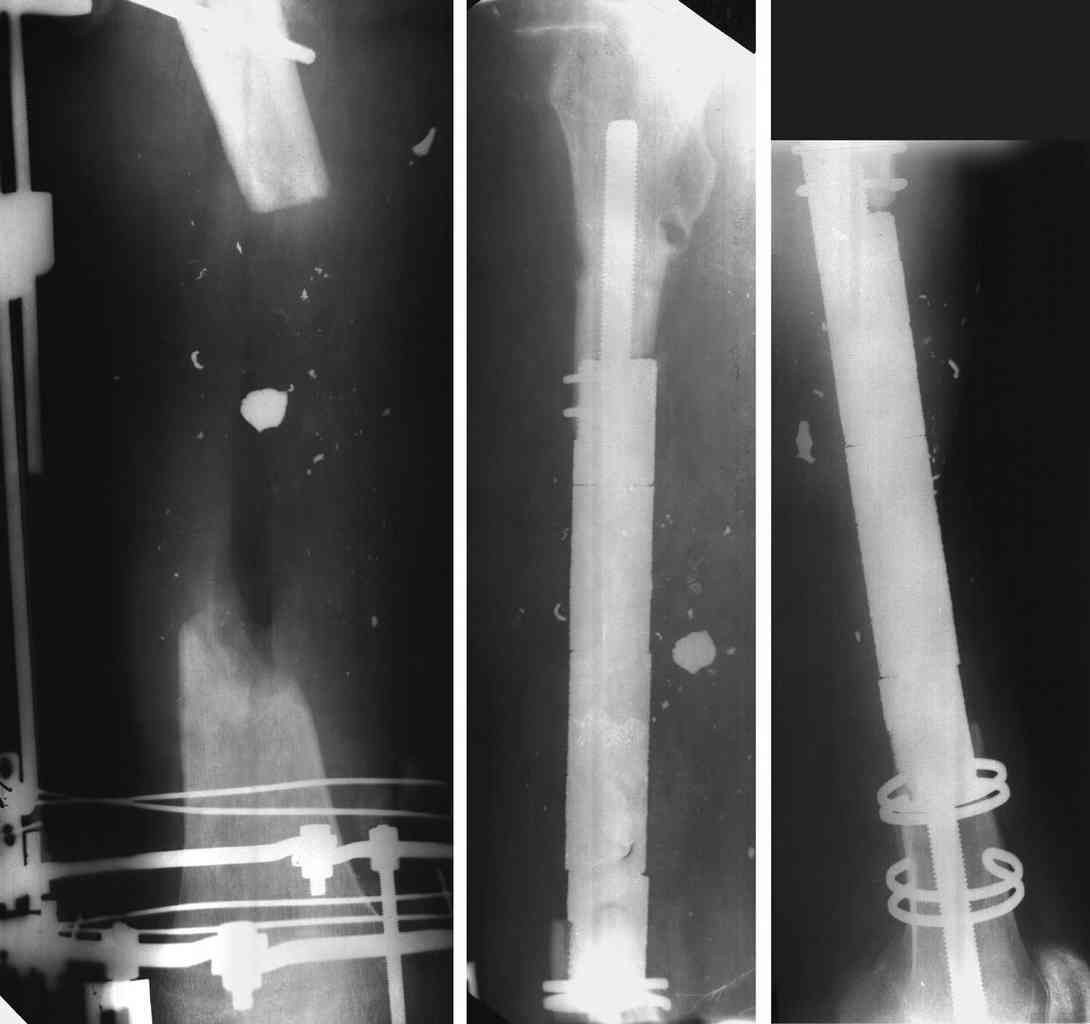

1 Ilizarov bone transport

3 Diaphyseal endoprosthesis - see photo (dangerous in soft tissue loss and infection)

I do an acute or accelerated shortening to reduce the gap as much as proximal, and distract proximally to restore length.

In this particular case, notice the change of fixator - orthofix type of unilateral fixator worked well initially but did not allow me to compress beyond a point, which is when I changed to an ilizarov for further compression at the gap/nonunion site.